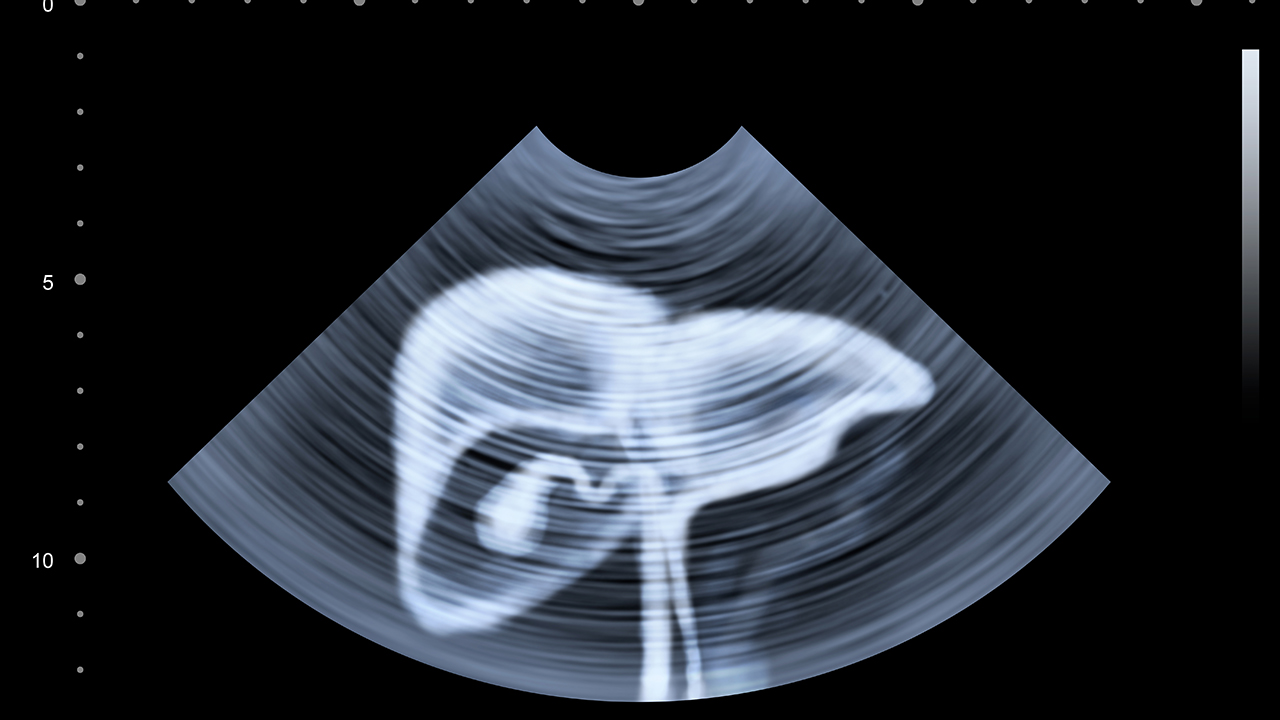

肝癌是一种常见的恶性肿瘤,其发病与慢性肝炎、肝硬化、黄曲霉毒素暴露等因素密切相关。早期诊断和规范治疗对提高患者生存率至关重要。

肝癌的预防与健康管理至关重要。建议高危人群定期进行肝脏超声和甲胎蛋白检查,做到早发现、早诊断、早治疗。日常生活中应避免饮酒、注意饮食卫生、避免食用霉变食物。慢性肝炎患者应积极治疗原发病,定期复查肝功能。保持良好的生活习惯,适当运动,增强免疫力,有助于降低肝癌发病风险。